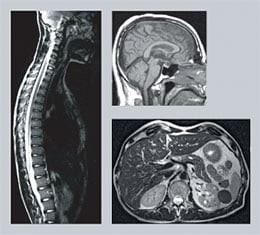

![]() |

| MRI is used for imaging of all organs in the body. |

Today, MRI is used to examine almost all organs of the body. The technique is especially valuable for detailed imaging of the brain and the spinal cord. Nearly all brain disorders lead to alterations in water content, which is reflected in the MRI picture. A difference in water content of less than a percent is enough to detect a pathological change.

Examination with MRI is especially valuable for detailed imaging of the brain and the spinal cord.